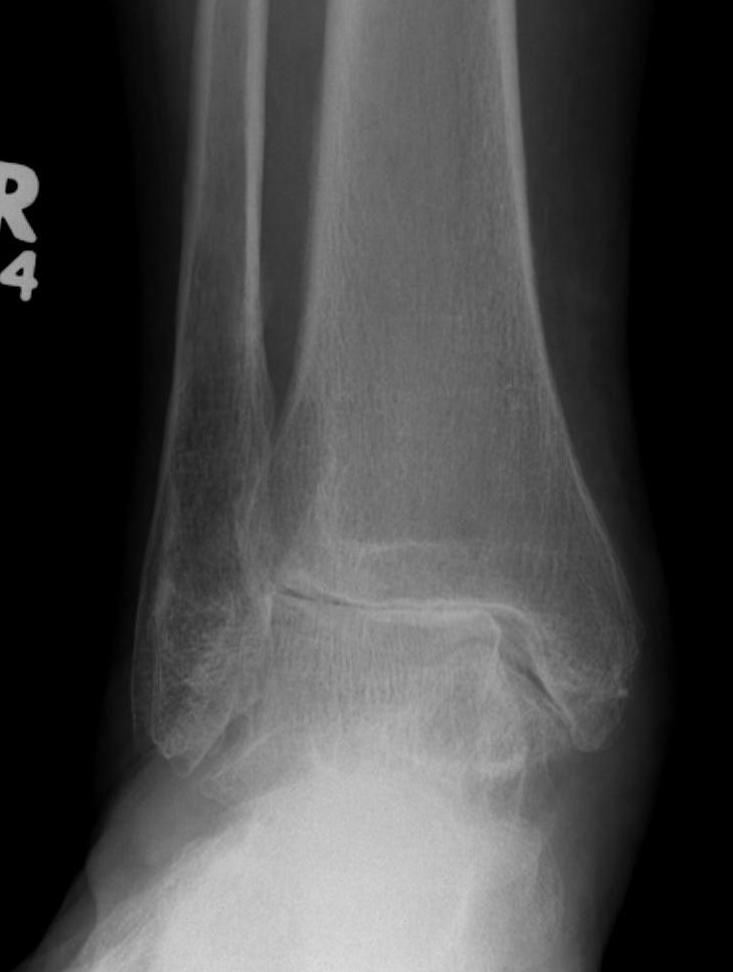

Contraindications

| Absolute | Relative |

|---|---|

|

Infection Charcot Poor soft tissue envelope Severe malalignment or instability Talus AVN > 1/3 |

Malalignment Poor bone stock Obesity Diabetes Smoking |

CT

Evaluate bone stock to determine if TAR is appropriate